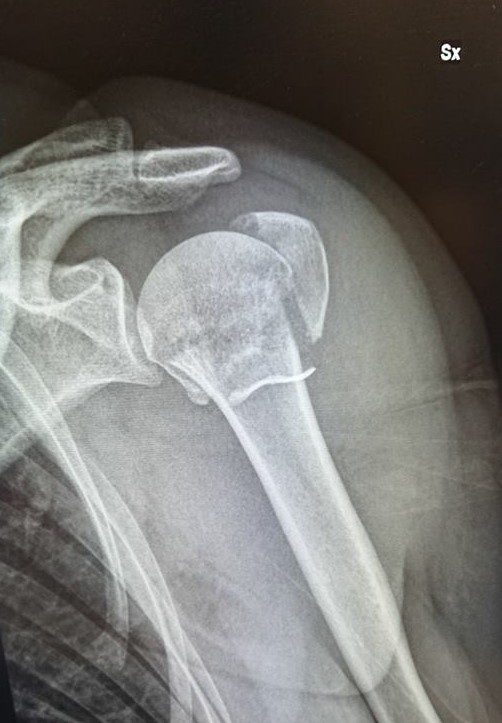

De voorlaatste skidag eindigde in mineur.

Iets wat in een bijna halve eeuw ski-ervaring nooit eerder gebeurde!

Even de controle kwijt?

Zelfs dat herinner ik me niet.

Maar het leverde wel een unieke vakantiefoto op!

Intussen zijn we alweer even thuis, is de operatie achter de rug, de eerste helse pijn met bijhorende misselijkheid is over en nog 5 weken van immobilisatie en verveling liggen voor me.

Nog een geluk dat het mijn linker is.

Meer en meer leer ik me 1-armig te behelpen maar makkelijk is anders.